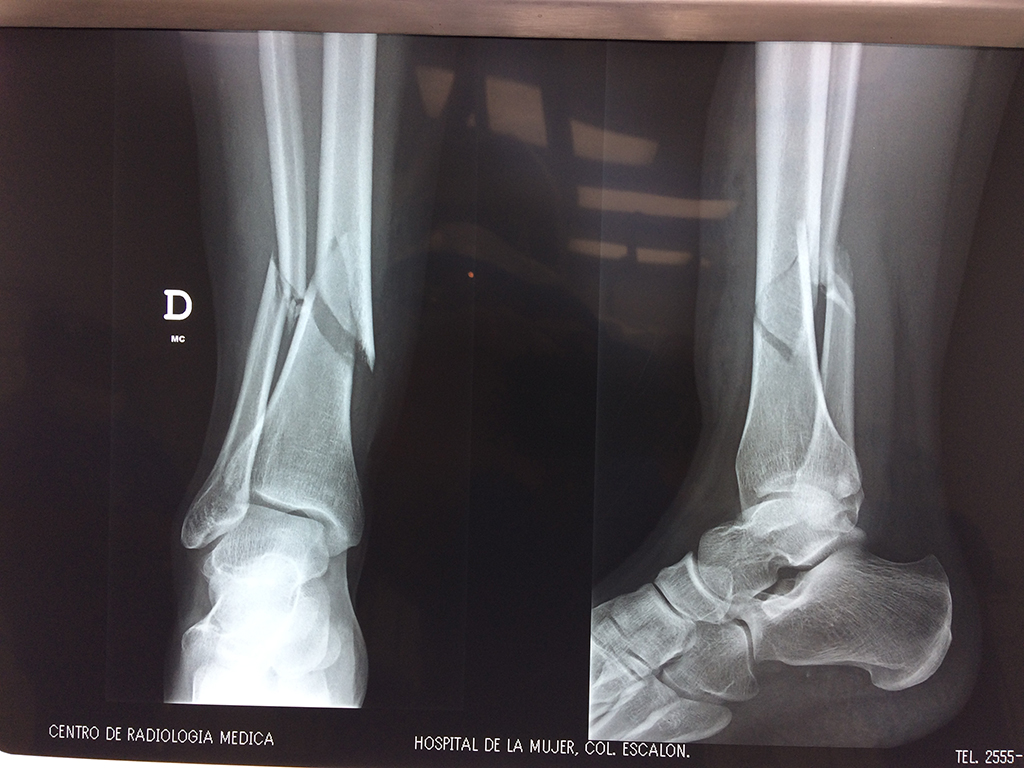

La mayor parte de las roturas implican a la parte proximal del hueso (parte del hueso próximo a la rodilla) o a la parte distal (parte del hueso cerca del tobillo).

Debido a la fina cobertura de piel que recubre la tibia y el peroné, las fracturas generalmente son abiertas, es decir, el hueso roto rasga la piel, atravesándola. Las fracturas de tibia y peroné generalmente se producen por un fuerte impacto o torsión.